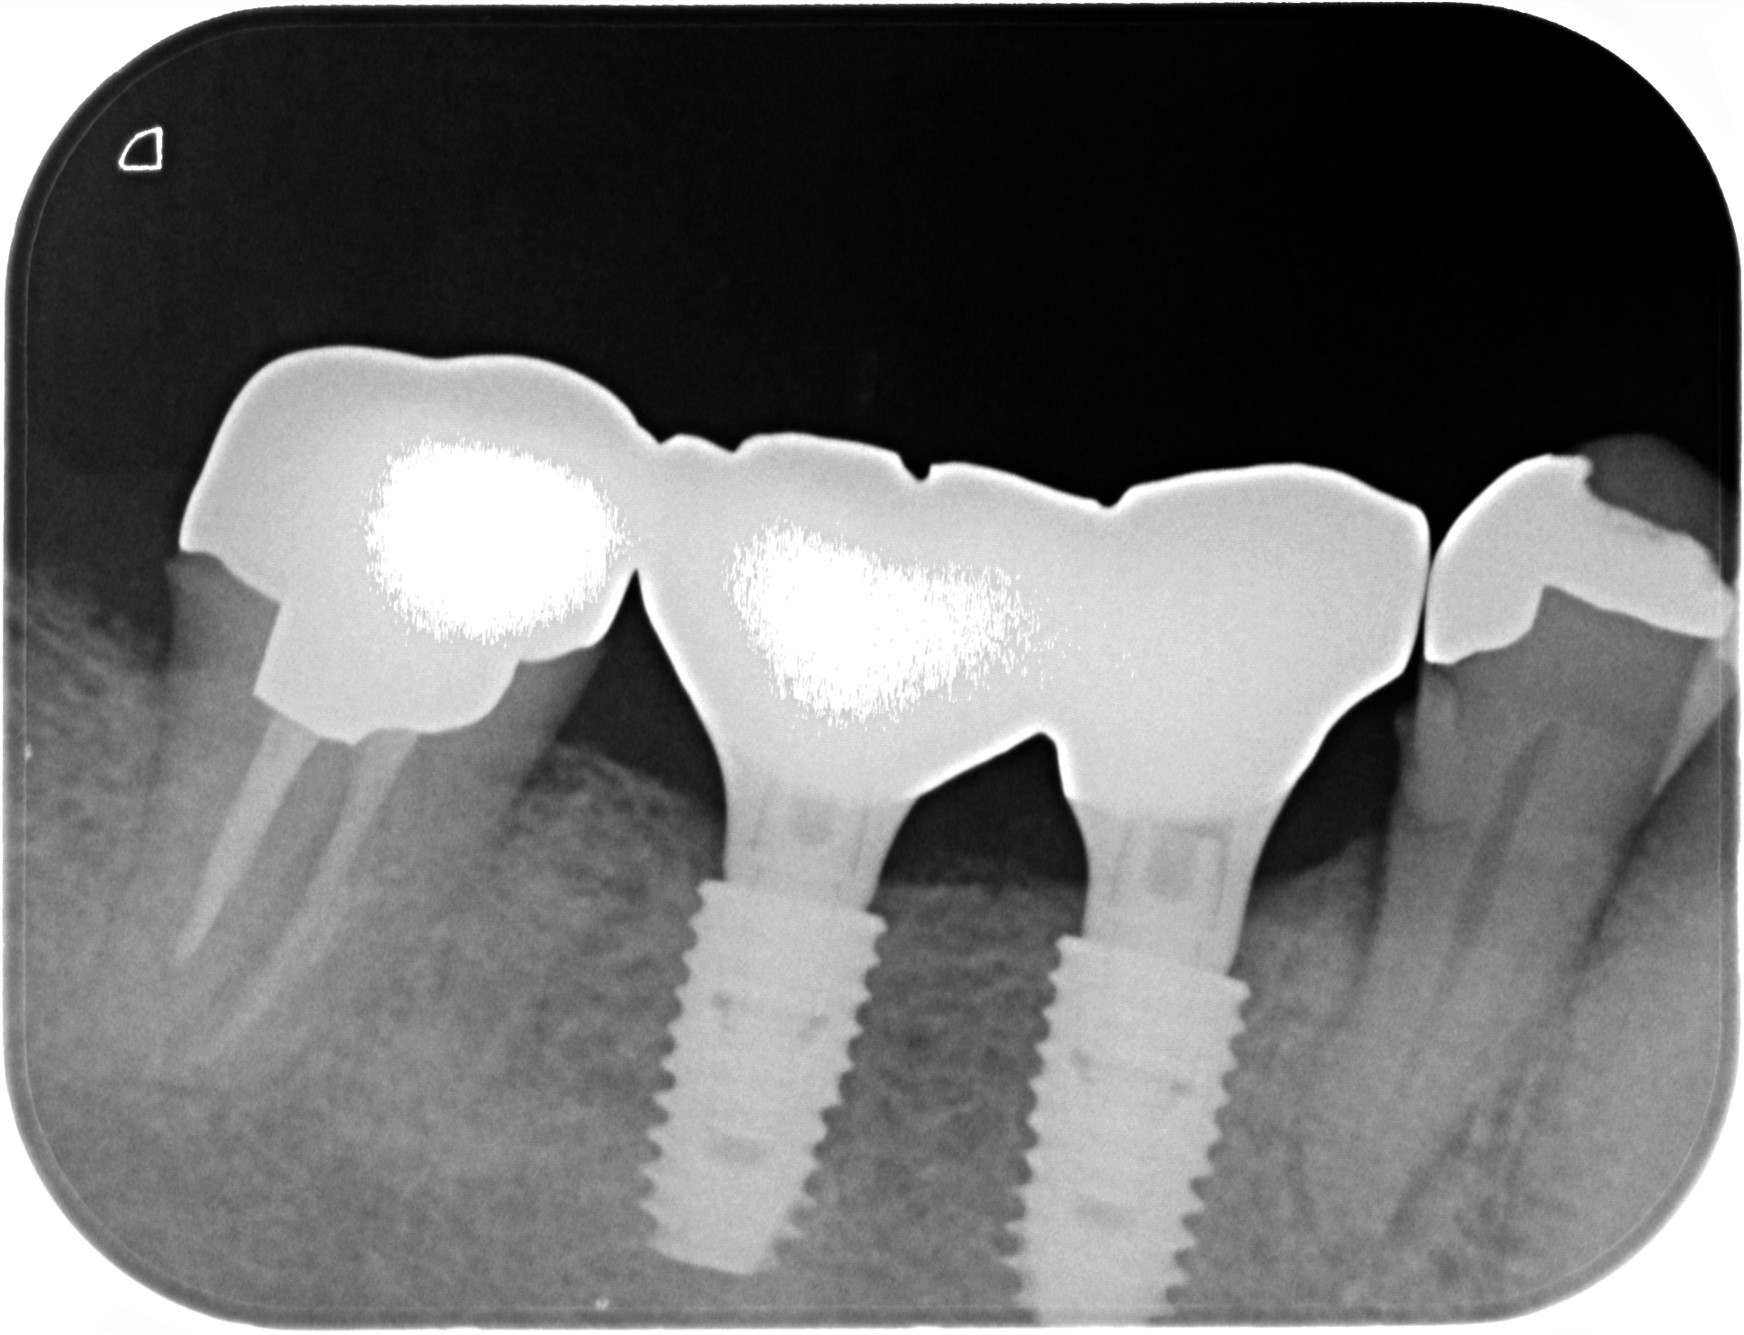

治療後レントゲン写真

- 右下56番パーシャルデンチャー部のインプラント治療

- 60代女性 右下56番にパーシャルデンチャーを装着しており機能及び審美的に問題を抱えている。

- まず、CT撮影による精密な骨の分析・治療計画を立てガイドを使いインプラント埋入しインプラントが骨と結合するのを待つ間に仮の歯を入れます。その後本歯を作成して装着しました。

- インプラント埋入からジルコニアセットまで三か月半

※自由診療となります - ■総額:¥660,000(税込み) ■内訳:埋入(ガイド込み)¥200,000×2、仮歯¥20,000×2、被せ物¥80,000×2